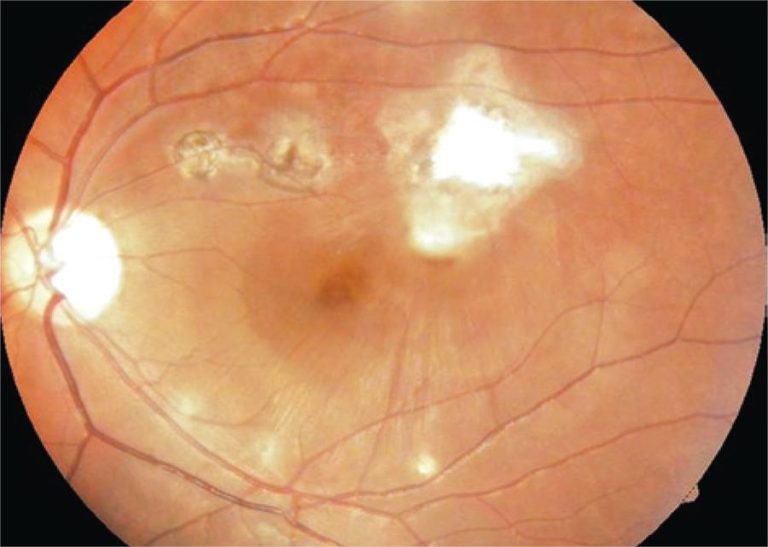

We report the case of a patient with congenital toxoplasmosis and submacular hemorrhage caused by a neovascular membrane who underwent an intravitreal injection of C3F8 and bevacizumab, and had a good visual recovery.

Keywords: Angiogenesis inhibitors; Case reports; Intravitreal injections/adverse effects; Retinal hemorrhage/etiology; Retinal neovascularization/complications; Tomography, optical coherence; Toxoplasmosis, congenital/etiology